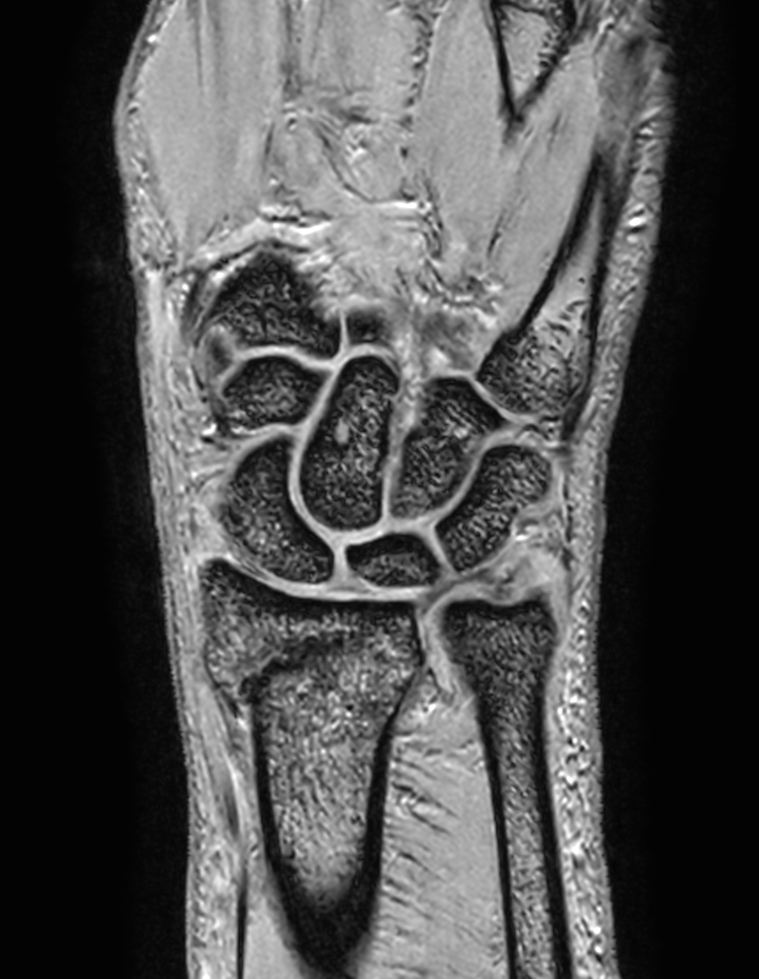

1Compared to scans without Compressed SENSE